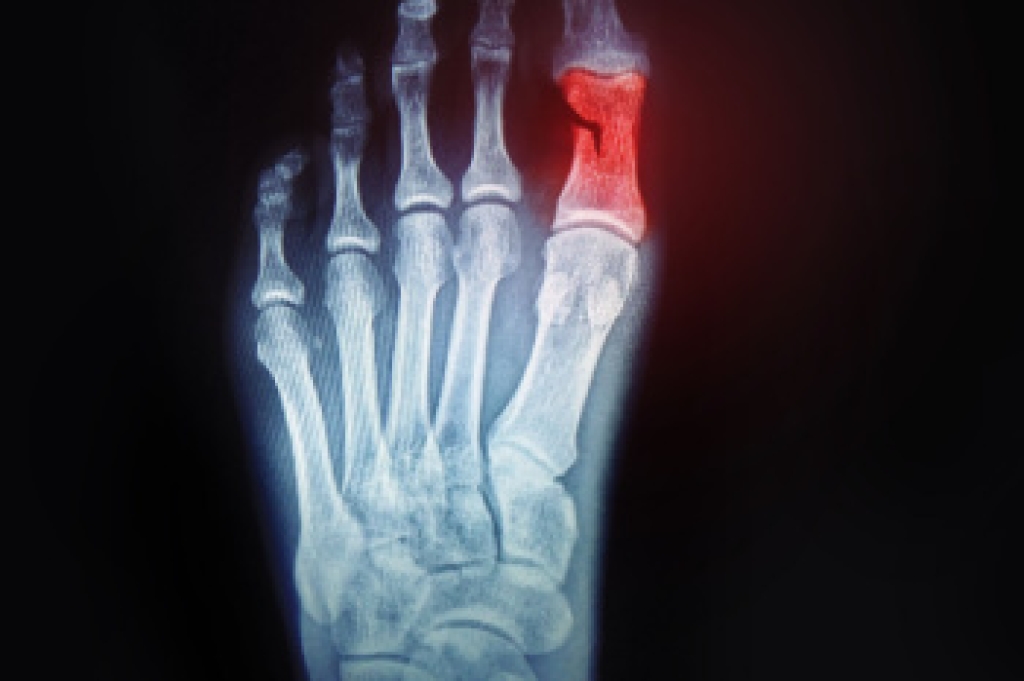

Treatment Options for Broken Toes

Broken toes can cause significant discomfort and limit mobility. Toe fractures usually occur from stubbing the toe, dropping something heavy on the foot, or sustaining a sports-related impact. Symptoms include swelling, bruising, and pain when walking or applying pressure. Diagnosis is confirmed through an exam and imaging to assess the extent of the fracture and determine if the bone is displaced. Stable, nondisplaced fractures may be managed with protective footwear to reduce movement and pressure, while displaced fractures often require a procedure to realign the bone. Fractures of the big toe tend to be more serious due to this toe’s role in balance and walking. Big toe injuries may require stabilization or even surgery if the damage is severe. A podiatrist can provide a proper diagnosis, realignment, and supportive devices to promote healing and prevent long-term complications. If you are experiencing pain from a broken toe, it is suggested that you make an appointment with a podiatrist for an exam, diagnosis, and treatment.

What to Know About a Broken Toe

Although most people try to avoid foot trauma such as banging, stubbing, or dropping heavy objects on their feet, the unfortunate fact is that it is a common occurrence. Given the fact that toes are positioned in front of the feet, they typically sustain the brunt of such trauma. When trauma occurs to a toe, the result can be a painful break (fracture).

Symptoms of a Broken Toe

- Throbbing pain

- Swelling

- Bruising on the skin and toenail

- The inability to move the toe

- Toe appears crooked or disfigured

- Tingling or numbness in the toe

Generally, it is best to stay off of the injured toe with the affected foot elevated.

Severe toe fractures may be treated with a splint, cast, and in some cases, minor surgery. Due to its position and the pressure it endures with daily activity, future complications can occur if the big toe is not properly treated.